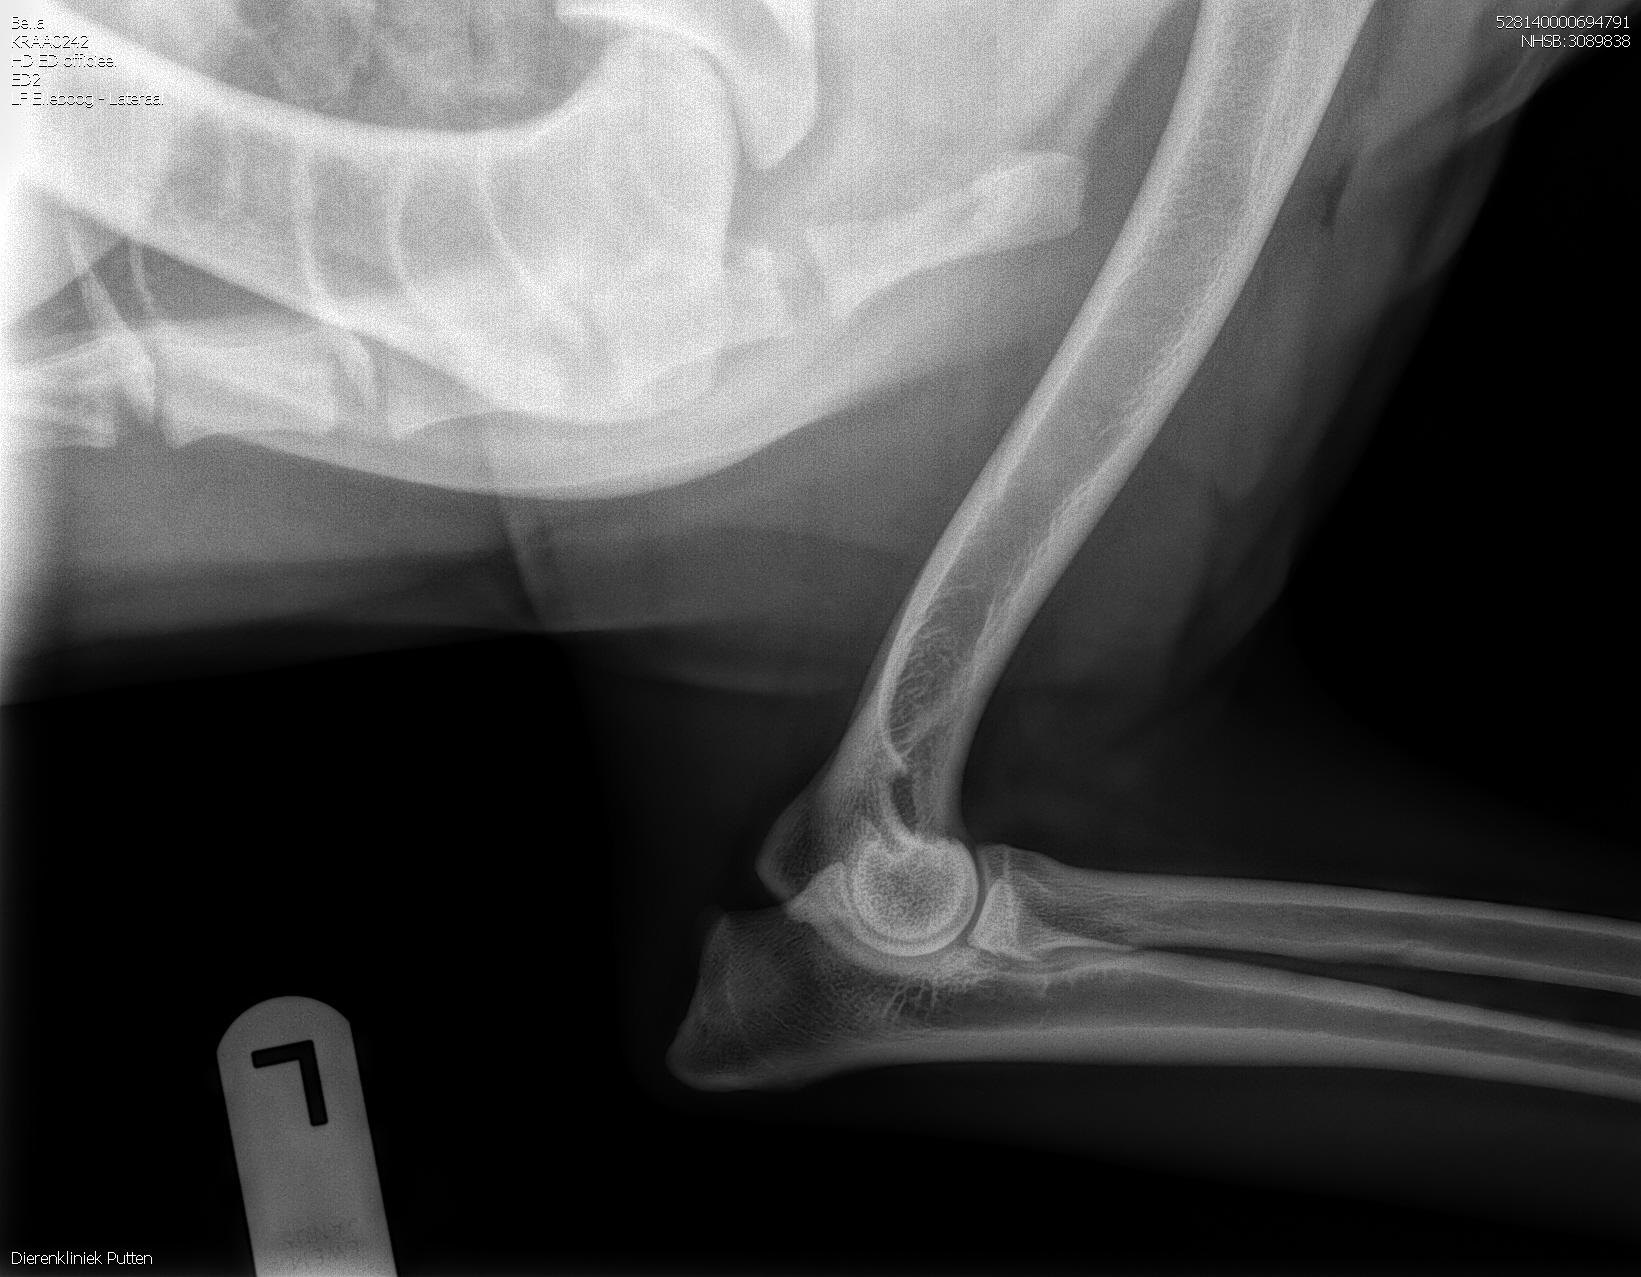

HD-A (Norbergwaarde 37.5, Botafw. 0), ED-0, Rug 100%

Röntgen foto’s Bella